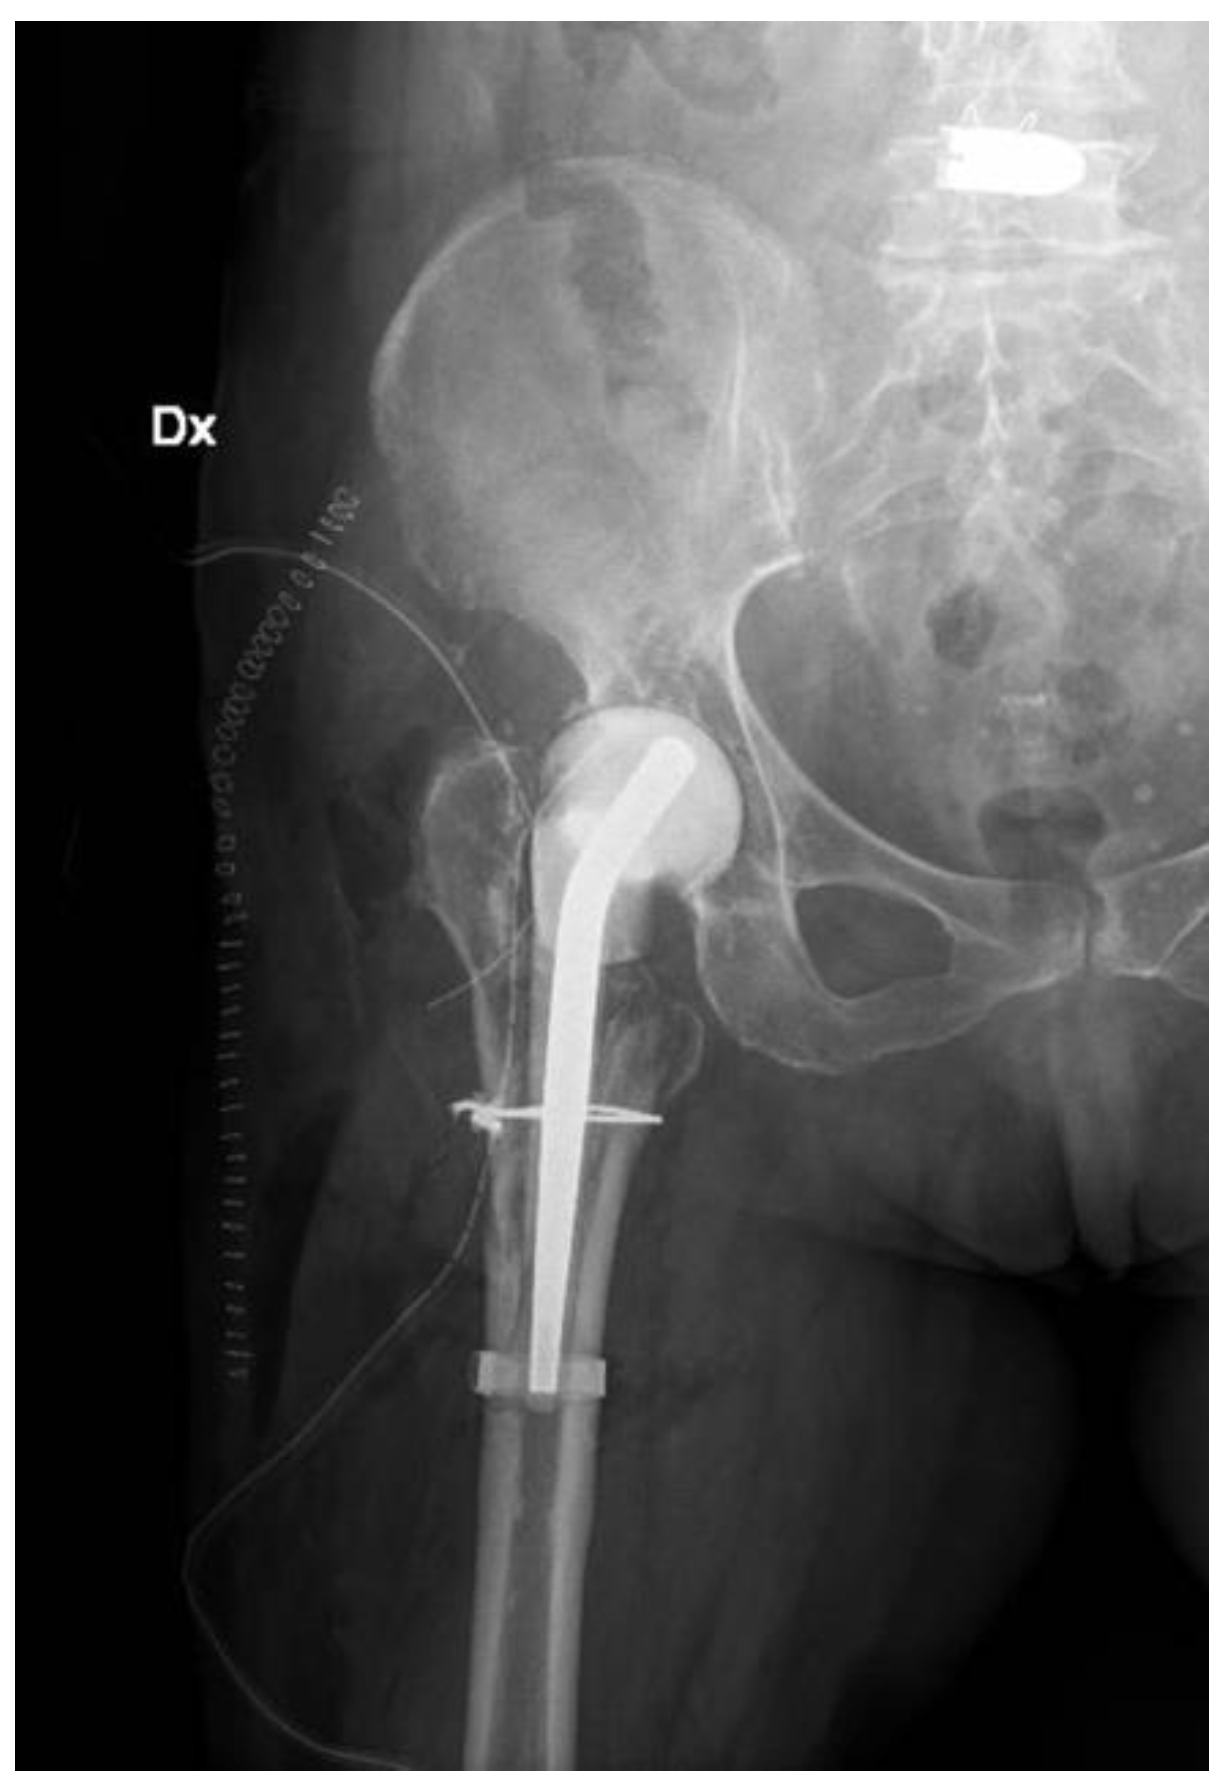

2. Case Report